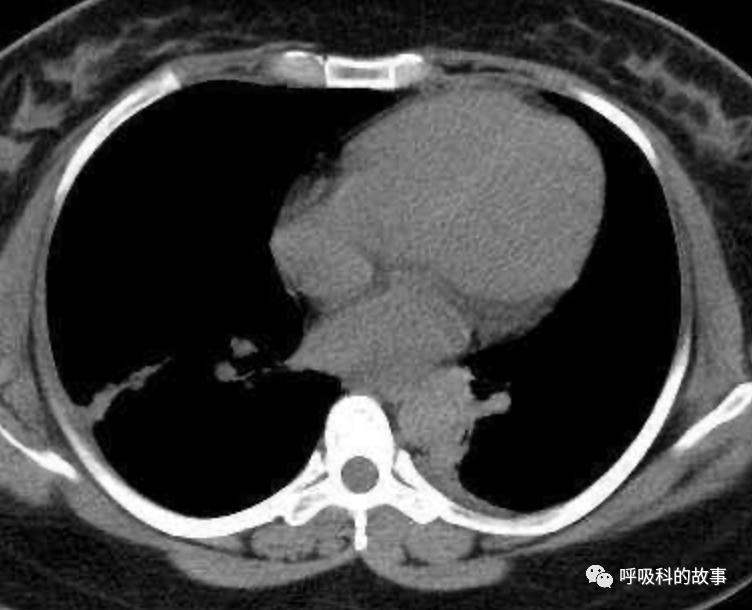

可是在6月26日(往院第18天)仍持续发热的情况下复查肺部CT,肺部病灶已明显吸收了。那么患者发热的原因到底是什么呢?为什么患者高热的情况下血白细胞不升反降,C反应蛋白也没有明显增高?这个时候消化科医生也迷茫了,这可怎么办?于是请感染科和呼吸科医生一起会诊,共商计策。